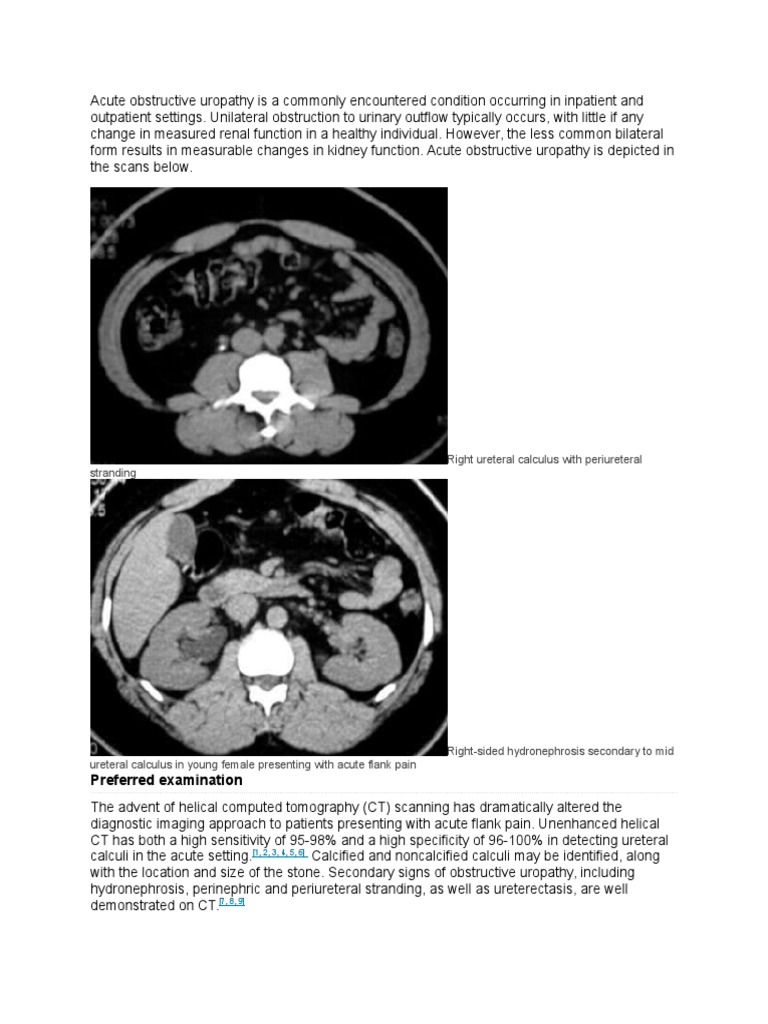

Hidronefrosis Medscape Kidney Ct Scan